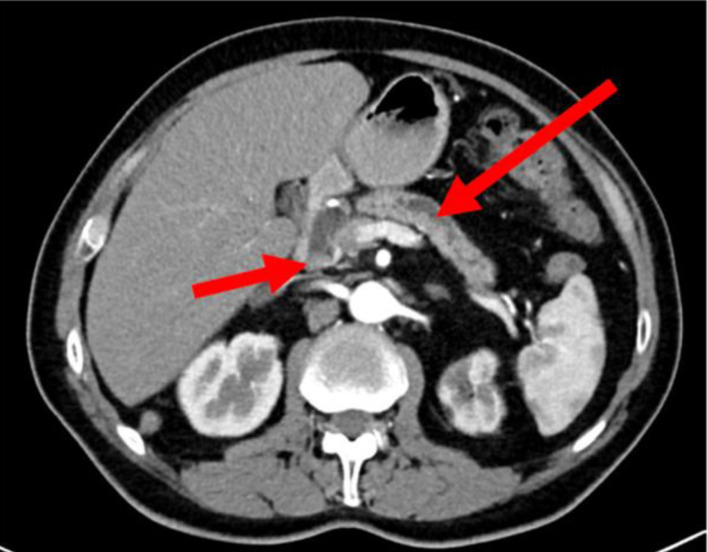

Pancreatic malignant tumors are diverse and characterized by aggressive nature with high mortality rates. Pancreatic ductal adenocarcinoma (PDAC) is the most common type of pancreatic malignant tumors and accounts for approximately 90% of pancreatic malignancies. A subtype of PDAC, diffuse type PDAC (DTP), is a very rare and underreported tumor, known for its aggressive traits. Although little data are available about this tumor subtype characteristics, it usually presents with distinct features that are different from the known ones in PDAC. Herein, we present a case of a 61-year-old male patient, who presented with abdominal discomfort, weight loss and newly diagnosed diabetes mellitus. An abdominal computed tomography (CT) scan showed an ill-defined mass at the uncinate process with diffuse dilatation of the main pancreatic duct. Endoscopic ultrasound (EUS)-guided fine-needle biopsy showed cellular atypia suspicious for malignancy. The patient underwent total pancreatectomy with Roux-en-Y reconstruction. His postoperative course was uneventful. The final histopathological report showed well-differentiated diffuse ductal adenocarcinoma involving the pancreatic head, neck and body.